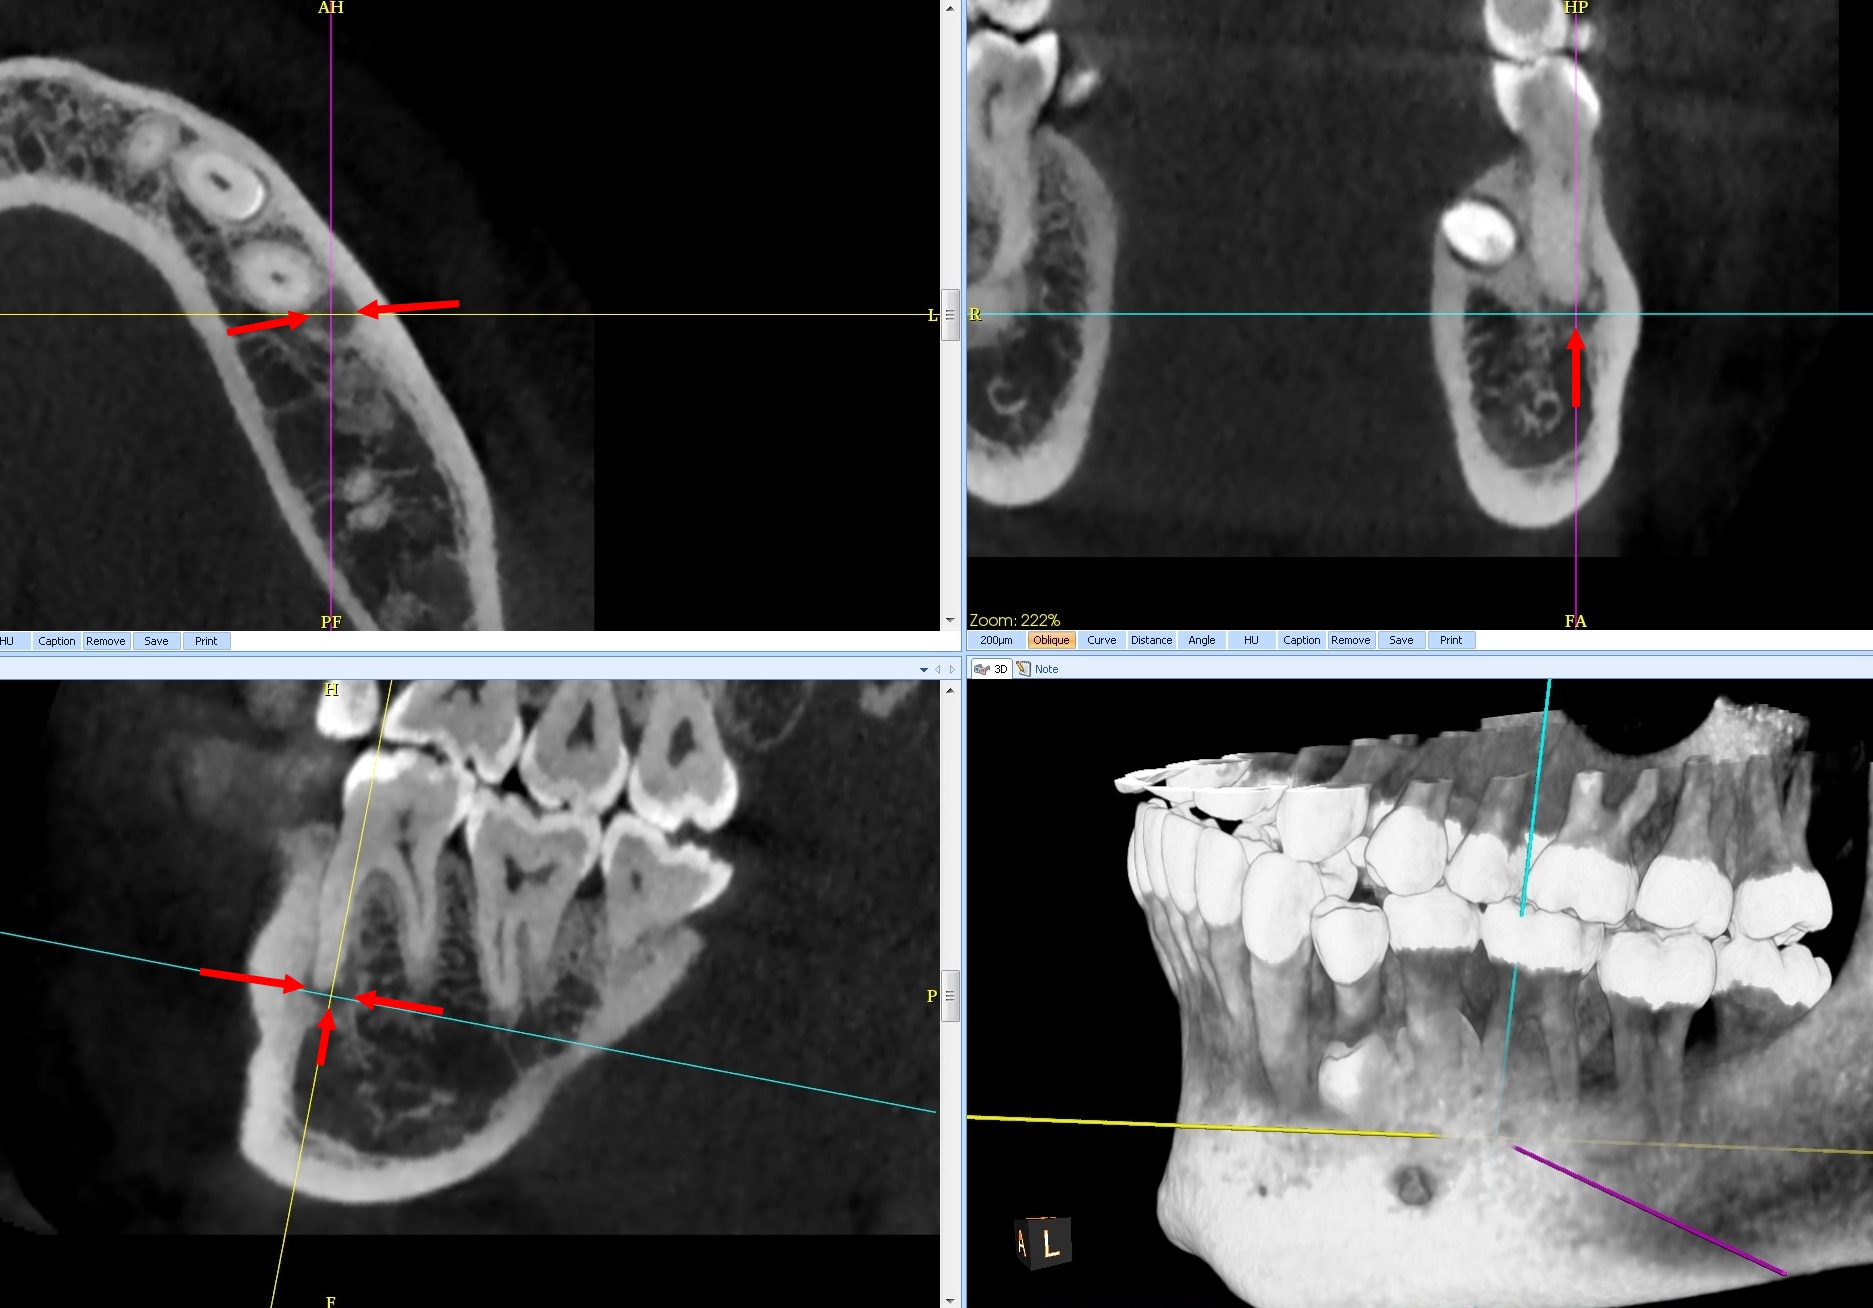

B. a. 46 : Lacunaire

b. 43 : En cocarde ou en cible à centre dense (lacune centrée par une zone centrale calcifiée).

c : Bloc incisif : Presque complètement dense, calcifiée (blanche), entourée d’un liseré clair (noir).

C. Le diagnostic est : Dysplasie osseuse (anciennement cémento-osseuse) floride.

– elles évoluent toujours sur dent vivante, en trois stades :

> stade I : dit « ostéolytique », lacune apicale, correspondant à du tissu fibreux, sur dent saine (Fig.1) ;

> stade II : intermédiaire, un dépôt de cément se formant au sein de la clarté apicale (Fig.2) ;

> stade III : hyperdensité apicale cernée par liseré clair périphérique (Fig.3)

B. La dysplasie osseuse (ou cémento-osseuse) floride (Fig.4). Elle touche surtout la femme noire d’âge moyen, affectant les deux maxillaires de façon plus ou moins diffuse et symétrique, associant des lésions de grande taille à tous les stades, pouvant s’infecter et se compliquer d’ostéite.